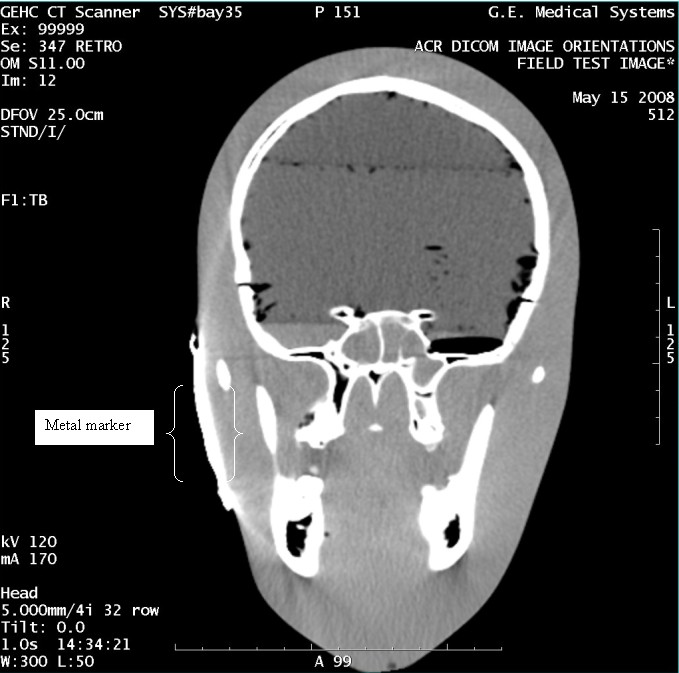

- With the support of the site personnel, examine the images sent

to the Review Station (i.e., 12 series, each with 1 image) and compare

their orientation to the images in this document.

- Each image contains a metal marker on the phantom's right cheek.

- Each image in this document contains a description of the expected

orientation of the metal marker (i.e. to prove Left and Right) as

well as the Posterior and Anterior orientation description.note:

The sample images included in this document use “R”, “L”, “P”, and “A” for “Right”, “Left”, “Posterior” and “Anterior” orientation. The Hospital Review Station may use a different style of annotation. The style used is not relevant to this procedure.

- Each image in this document has sufficient space to store the observed results for up to 4 Review Stations.

- Enter ‘Y’ in the space to indicate the observed result matches the expected.

- Enter ‘N’ in the space to indicate the observed result does not match the expected.

- Enter “NA” in the space if a column is not being used.

- Repeat for each destination.

Figure 10. Exam 99999, Series 347